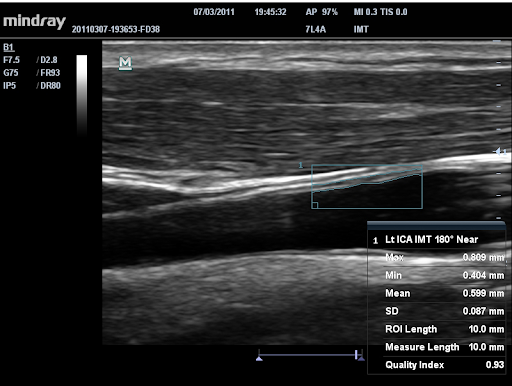

Авто IMT (толщина интима-медиа)

Автоматическое измерение толщины задней и передней стенок, дающее точные сведения о состоянии сонной артерии.

Линейный датчик Mindray 7L4A, (5.0/7.5/10.0MHz), 35 мм